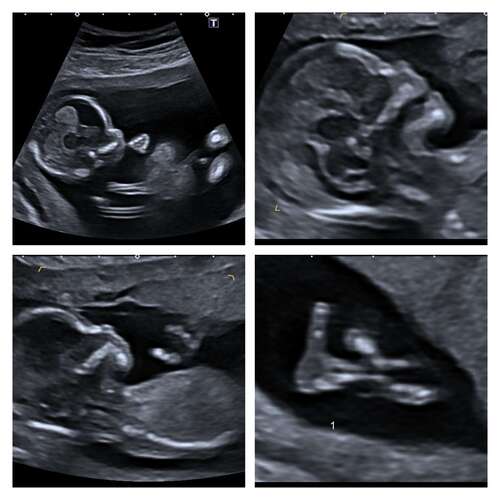

Hier ook goede echo met 13+5 zo blij!! Als iemand wil raden of het een jongetje of meisje is: ik ben heeel benieuwd wat jullie denken, moet nog even wachten tot de geslachtsecho op 5 januari.